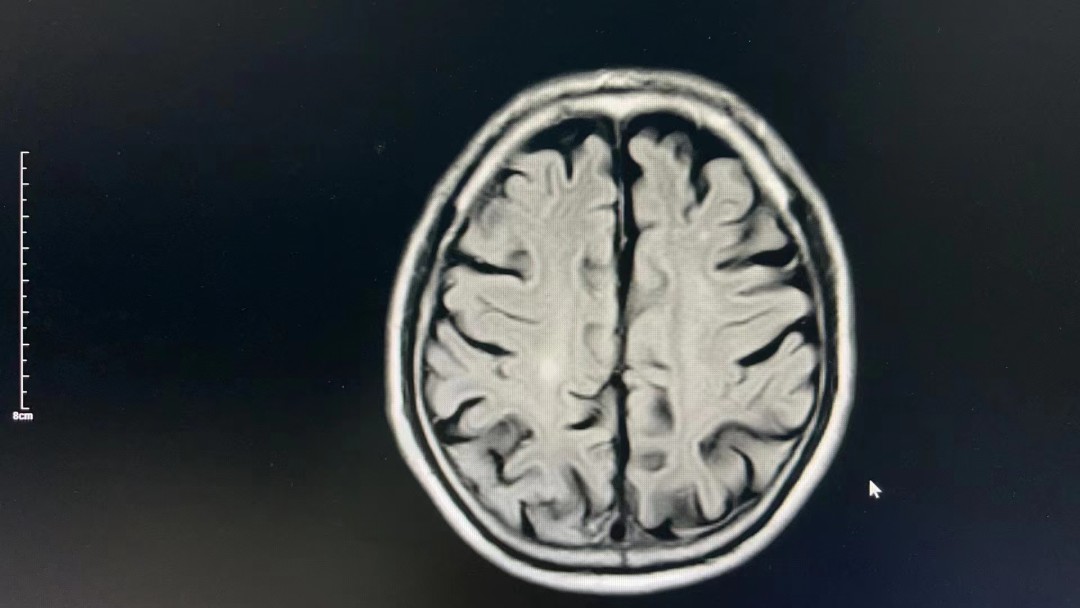

患者后续收治到西医内科继续治疗,完善头颅核磁检查后考虑:“右侧大脑半球多发继续脑梗死”,此次治疗对患者远期生活质量获益较大,减少致残率,家属表示很感谢!